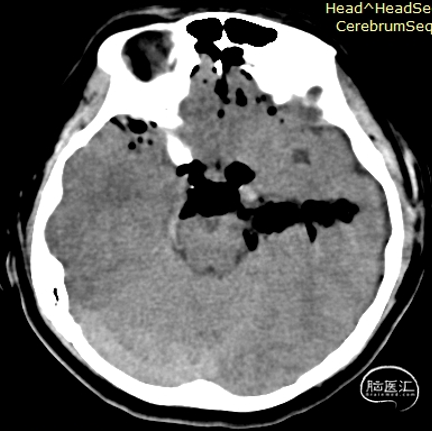

术前影像:

左侧海马旁回海绵状血管瘤。